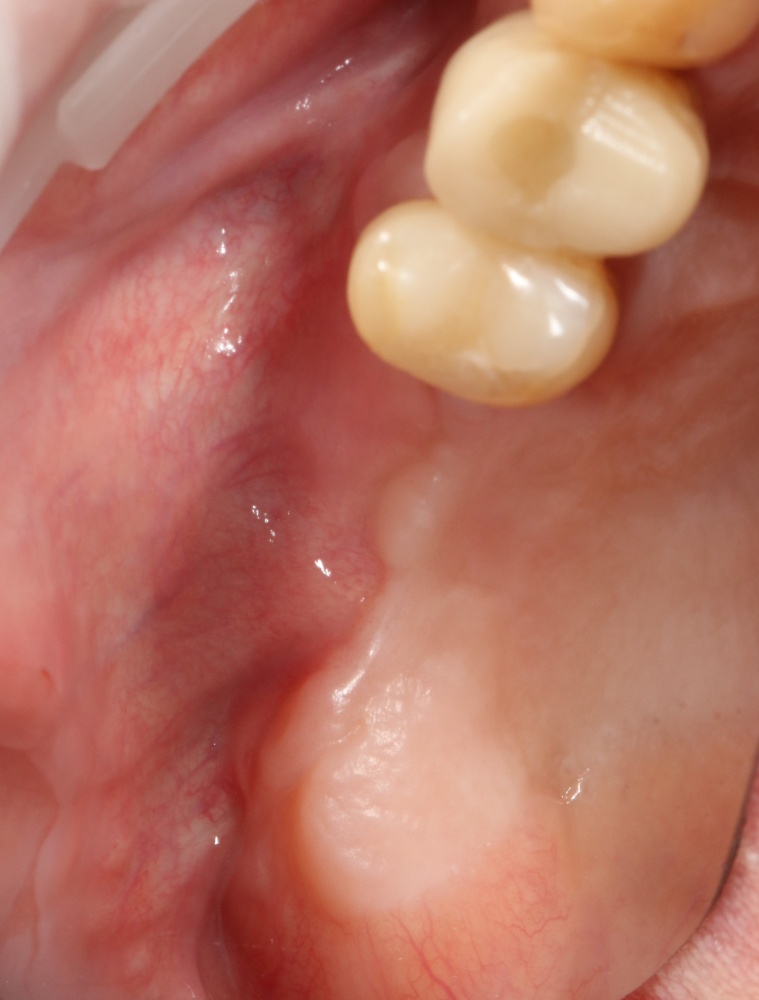

Через пару недель область, где мы провели уже две операции, выглядит примерно так:

или, если снять формирователи:

Можно передавать пациента ортопеду для временного протезирования. Что он и делает:

Можно приступать к формированию десны. Напомню, что для длительного и счастливого функционирования имплантов в боковом участке необходима кератинизированная десна в объеме не менее 2 мм вокруг шейки импланта. Где ее взять? Все там же, с небного края альвеолярного гребня!

Именно поэтому при формировании десны мы смещаем разрез настолько внутрь, насколько это вообще возможно. В целом, он не отличается от того, что мы делали при первой операции.